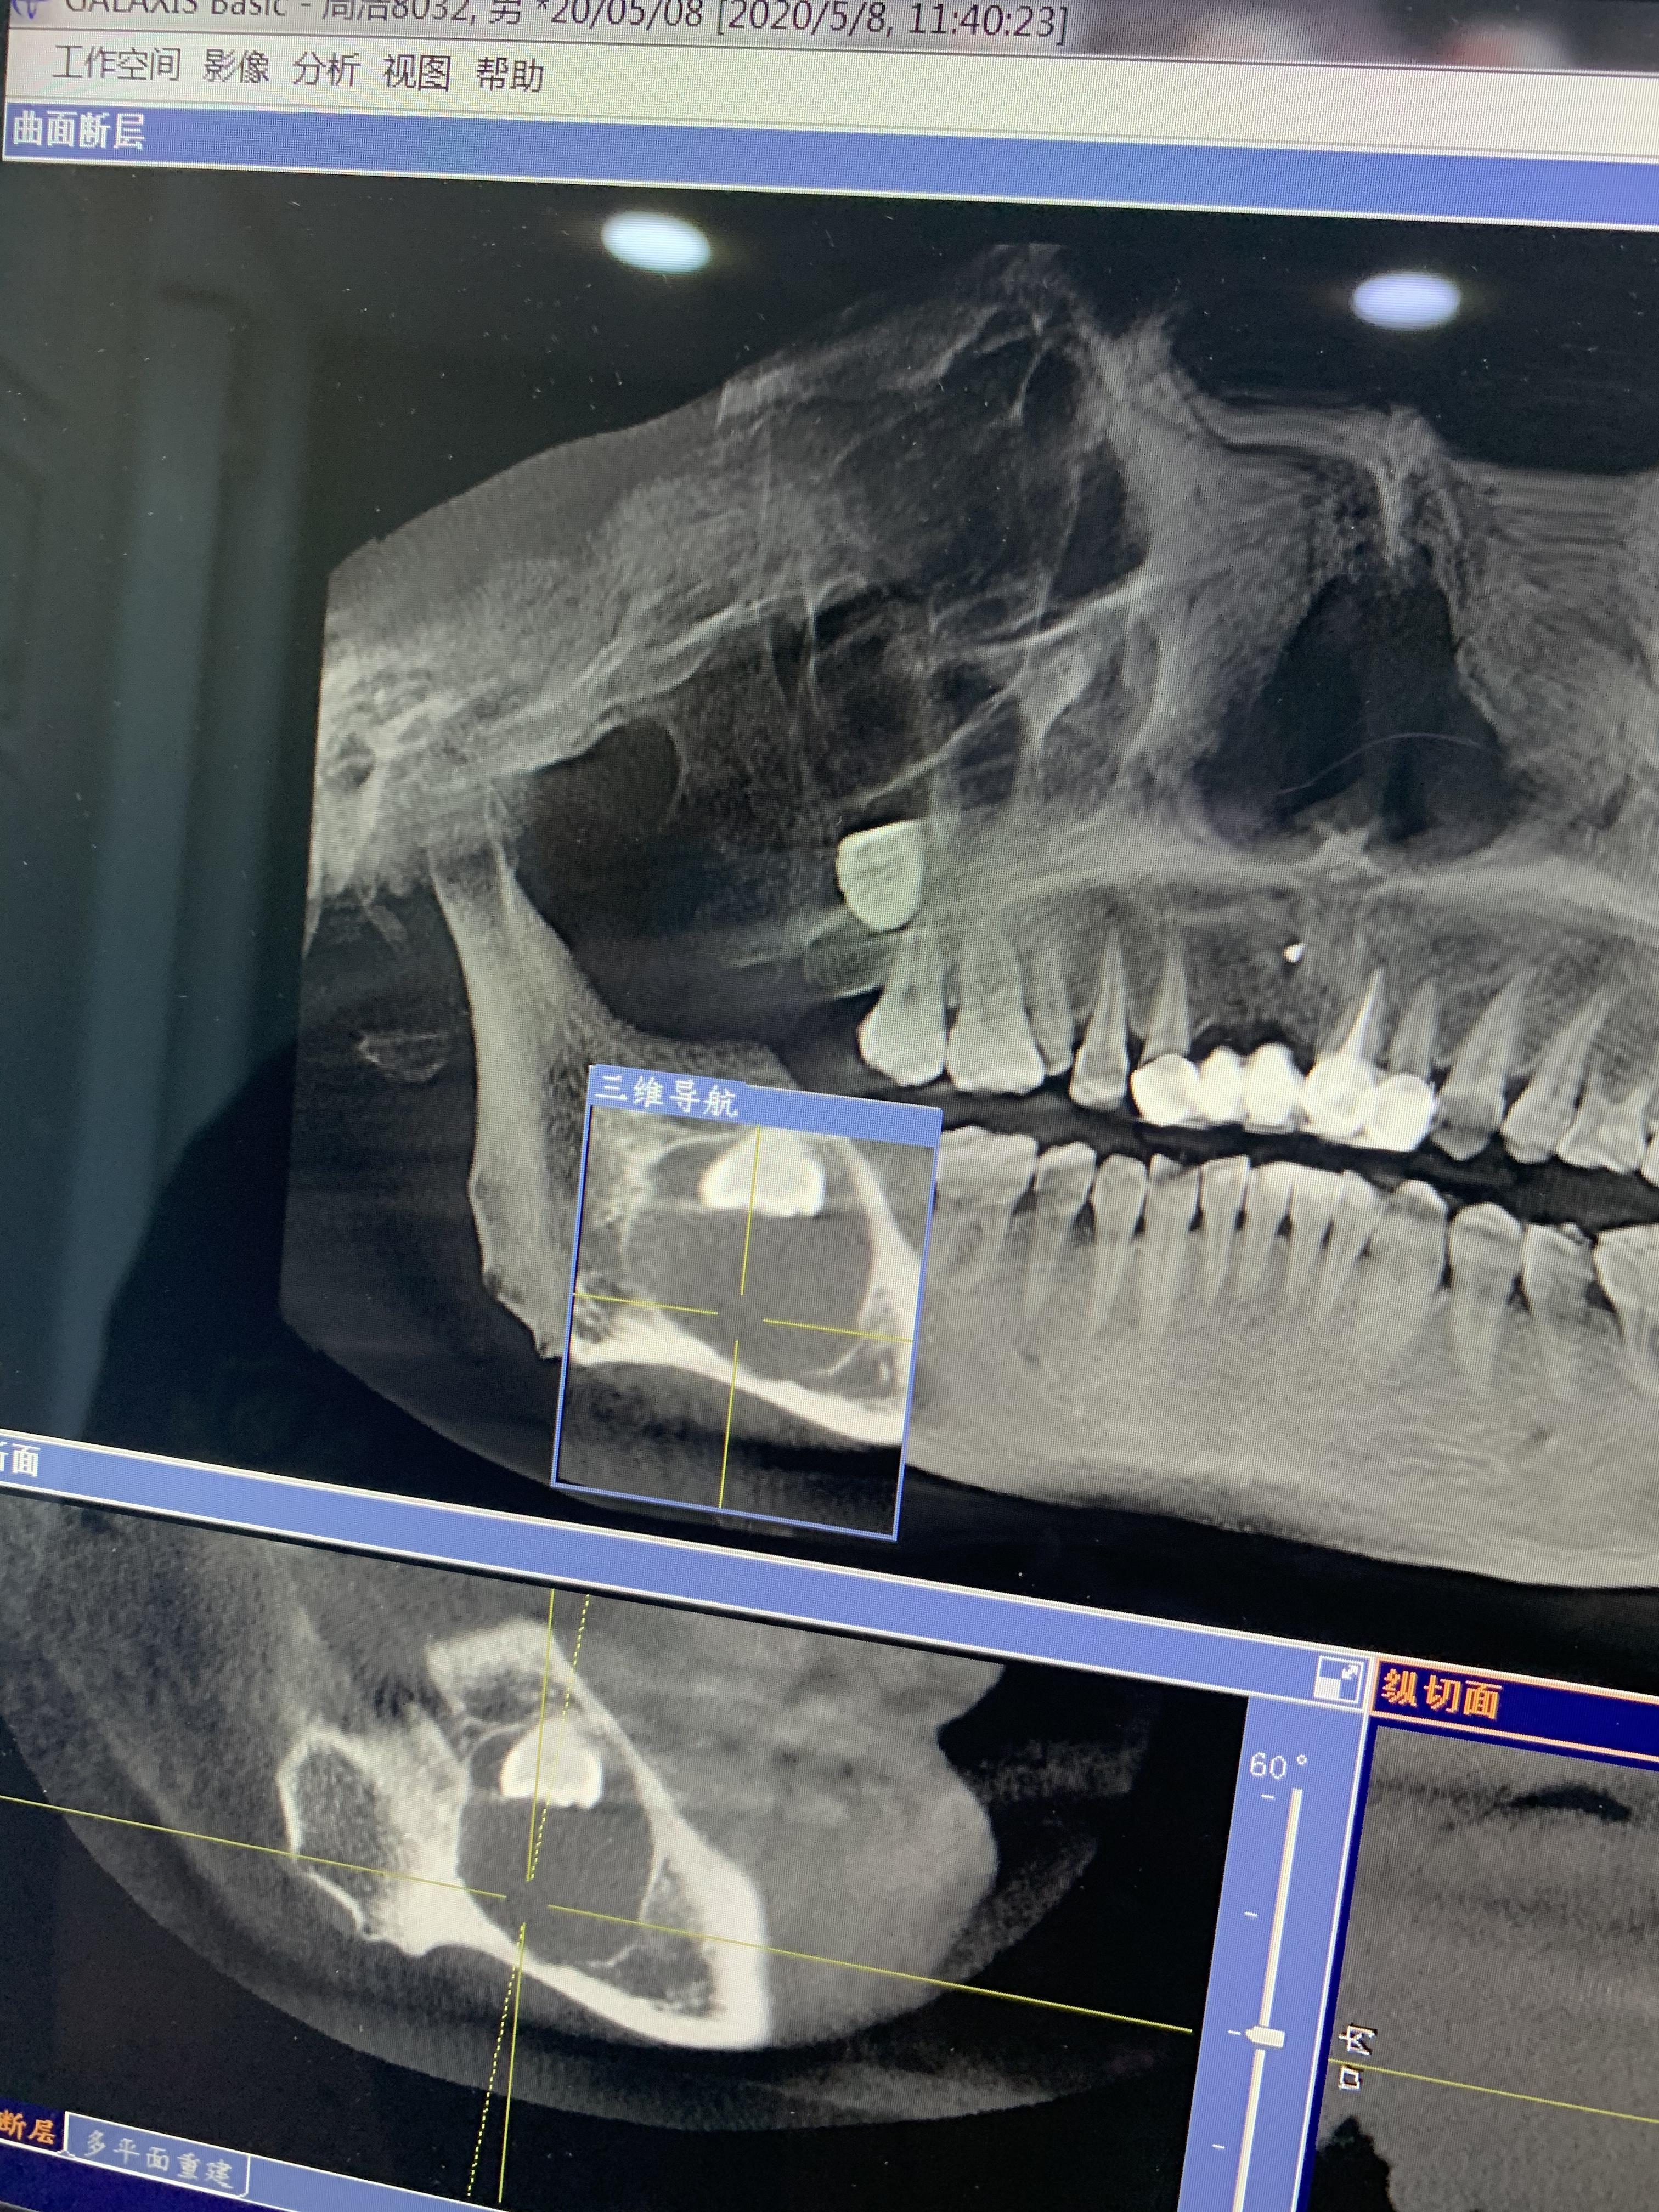

方框內(nèi)圓形的就是囊腫,從邊緣看,骨頭已經(jīng)很薄了

右下頜囊腫,倒阻生牙